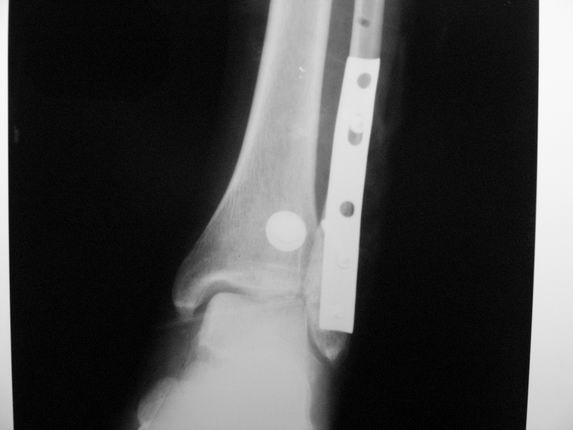

Re: Консолид. перелом г/ стопного

послал Алексей Минервин 16 Март 2006, 17:06

Уважаемые коллеги! Как и обещал, представляю плоды своей работы. Хвалиться особо нечем. Пошли задним

доступом сначала к м/берцовой кости, благодаря смещению линию перелома удалось сразу дифференцировать и по ней узким долотом (без молотка) мобилизовали отломки. Затем выделили задний край, там было проще пройти по линии перелома. Далее пластина по задней поверхности в дистальный отломок, винт проксимальнее пластины и дистрактором с трудом растянули отломки, ощущение было идеальной репозиции м/берцовой кости( доступен осмотр по задней и наружной поверхности), далее винты стандартно. Кстати, положение больной на боку: очень неудобно, но по-другому потом не повернуть на спину, чтобы сделать снимки в стандартных проекциях (ЭОПа нет). Затем дистрактор (два полукольца, спицы), репозиция заднего края, спонгиозный винт с шайбой, слишком проксимально, поэтому + еще один. Доступ к дельтовидной связке: рубец в передней порции, частично иссечен, шов. В общем, длительность операции 3,5 часа, а сказать, что все задуманное получилось, не могу.

А.Минервин.